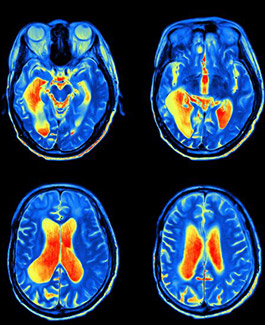

Neuroimaging

Our focus is to investigate differences in brain function in ME/CFS, long COVID and GWI using ultra-high field 7 Tesla MRI.

NCNED is the first to report:

- Impaired brain functional connectivity in ME/CFS and long COVID.

- Reduced white matter in the brainstem and a compensatory increase in white matter in the cortex – the action part of the brain.

- Brain structural changes in ME/CFS and long COVID participants.

Expert: Associate Professor Leighton Barnden and Dr Kiran Thapaliya